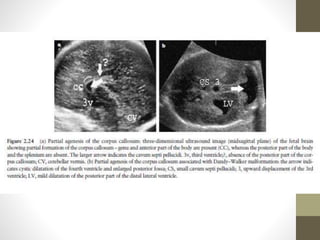

AGENESIS OF CORPUS CALLOSUM

โ€ข The normal development of the corpus callosum begins anterior

partial (affects dysgenesis posterior aspects) or complete.

โ€ข US Features

โ€ข The corpus callosum is not visible in complete agenesis.

โ€ข โ€ข Colpocephaly

โ€ข โ€ข Lateral ventricles are displaced laterally (parallel lateral ventricles).

โ€ข โ€ข Enlarged 3rd ventricle expands superiorly (high riding third

ventricle).

โ€ข โ€ข Angulated frontal horns (coronal view)( U or VIKING HORN

CONFIGURATION)

โ€ข โ€ข Abnormal (sunburst) gyral pattern in interhemispheric fissure is a

late feature.

โ€ข โ€ข The presence of a cavum septum pellucidum excludes complete

Agenesis

โ€ข Common associations include:

โ€ข Dandy-Walker (DW) syndrome

โ€ข Holoprosencephaly

โ€ข Heterotopias

โ€ข โ€ข TVS scaning is often helpful for early diagnosis.

โ€ข โ€ข Associated with pericallosa llipoma (hyperechoic)